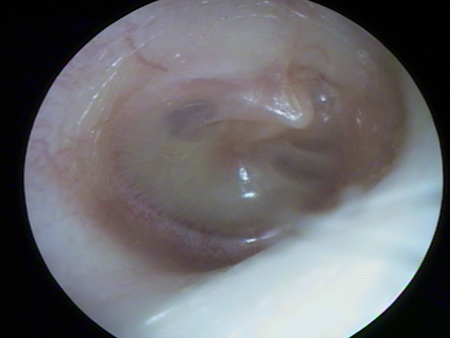

Otitis media with effusion

Appearance of tympanic membrane in otitis media with effusion, showing bubbles and serous fluid in the inferior aspect

Farboud A. BMJ. 2011;343:d3770